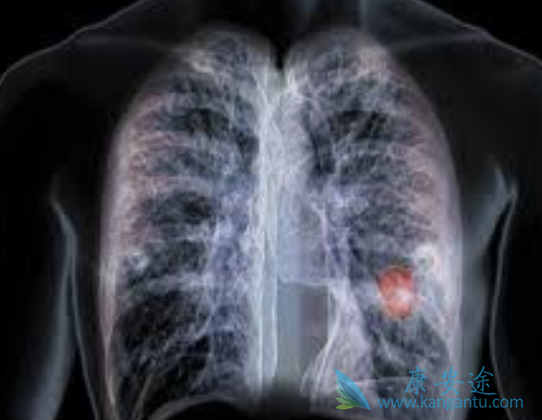

铂类是目前晚期非小细胞肺癌(non-small-celllung cancer,NSCLC)一线化疗的首选药物,多项研究表明紫杉醇、多西紫杉醇、吉西他滨及长春瑞滨等均可与铂类联用,且此类药物在无进展生存期(PFS)和总存期(OS)方面无明显差异。纳米白蛋白结合型紫杉醇(Nanoparticle albumin bound paclitaxel,nab-P)是一种无需借助溶剂的紫杉醇,大量研究证实了其对比溶剂型紫杉醇的疗效与安全性优势。吉西他滨联合顺铂治疗NSCLC也是目前国内外临床实践的热点,但尚未有研究对nab-P与吉西他滨的获益及风险进行直接比较。

本项随机II期临床研究直接比较了nab-P(单周用药)联合顺铂与吉西他滨联合顺铂在晚期NSCLC患者一线治疗中的疗效与安全性,结果表明两种方案在有效率、生存获益及安全性方面均无明显差异。但在不同组织学分类及基因突变人群中,二者的生存获益存在差异,对于体能状态较好,或EGFR突变的患者而言,使用nab-TP方案治疗可获得更长的生存期。

本研究发现一项重要结果,即与吉西他滨/顺铂相比,nab-P /顺铂方案可为EGFR突变的患者群体带来明显生存获益,此前尚无EGFR突变与nab-P联合顺铂疗效相关性的报道。目前,针对EGFR突变患者的靶向药物不断被开发,尽管已证实此类药物的强大疗效与中度不良反应,但若能找到合适的化疗方案也不失为一种替代选择,尤其是在EGFR-TKIs耐药后。考虑本研究纳入的样本量较小,未来需要更大样本量的研究来进一步验证nab-P /顺铂方案在EGFR突变患者中的生存获益及潜在机制。

nab-P(单周给药)联合顺铂方案一线治疗晚期NSCLC患者,在疗效与耐受性方面与吉西他滨联合顺铂相当。两种治疗方案基于EGFR突变和PS状态的生存获益差异,为未来临床研究进一步探讨其潜在机制奠定有力依据。